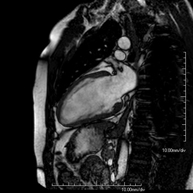

És una prova diagnòstica no invasiva que obté informació morfològica i funcional del cor i les estructures adjacents. D'aquesta manera es poden diagnosticar diferents patologies congènites i adquirides, o bé realitzar controls en pacients amb patologia prèvia ja coneguda. En la gran majoria de casos és necessari l'ús de contrast intravenós (Gadolini) per completar l'estudi, un tipus de contrast que rarament produeix reaccions adverses. Durant la prova el tècnic li demanarà diverses vegades que aguanti la respiració durant 10-15 segons per obtenir les imatges tant clares sigui possible. No es necessita preparació prèvia per part del pacient. La durada de la prova és de 45 – 60 aproximadament. Està contraindicada en pacients amb marcapassos. El pacient haurà d'avisar en cas que porti implants metàl·lics i/o clips quirúrgics. - RM cardíaca amb estrès miocardi

This non-invasive diagnostic test yields morphological and functional information about the heart and adjacent structures. In this way, different congenital and acquired pathologies can be diagnosed, or checks can be carried out on patients with previously known pathologies. In the vast majority of cases, intravenous contrast (gadolinium) is required to complete the study. This type of contrast rarely causes adverse reactions. During the test, the technician will ask the patient to hold their breath several times for 10–15 seconds to obtain the clearest images possible. No prior preparation is required by the patient. The test lasts approximately 45–60 minutes. It is not recommended for patients with pacemakers. Patients should nevertheless inform the doctor if they have metal implants and/or surgical clips.